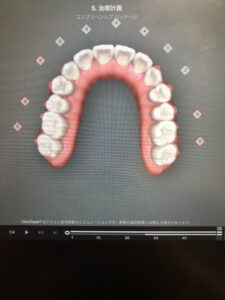

20枚目も、正面だと変化がわかりにくいですが、下から見ると隙間のある箇所が変わっているのがわかります。

30枚目になると、ようやく正面からでも変化がわかるようになりました。

今回はアライナー10枚ごとの歯の動きを見ていただきましたが、実際は1枚ずつ歯の動きをご覧いただけます。

どのように歯を動かしてどんな歯並びになるのかを患者様と一緒に見ることができるので、自分の理想の歯並びになるのか確認していただいた上で矯正治療を始めることができます。